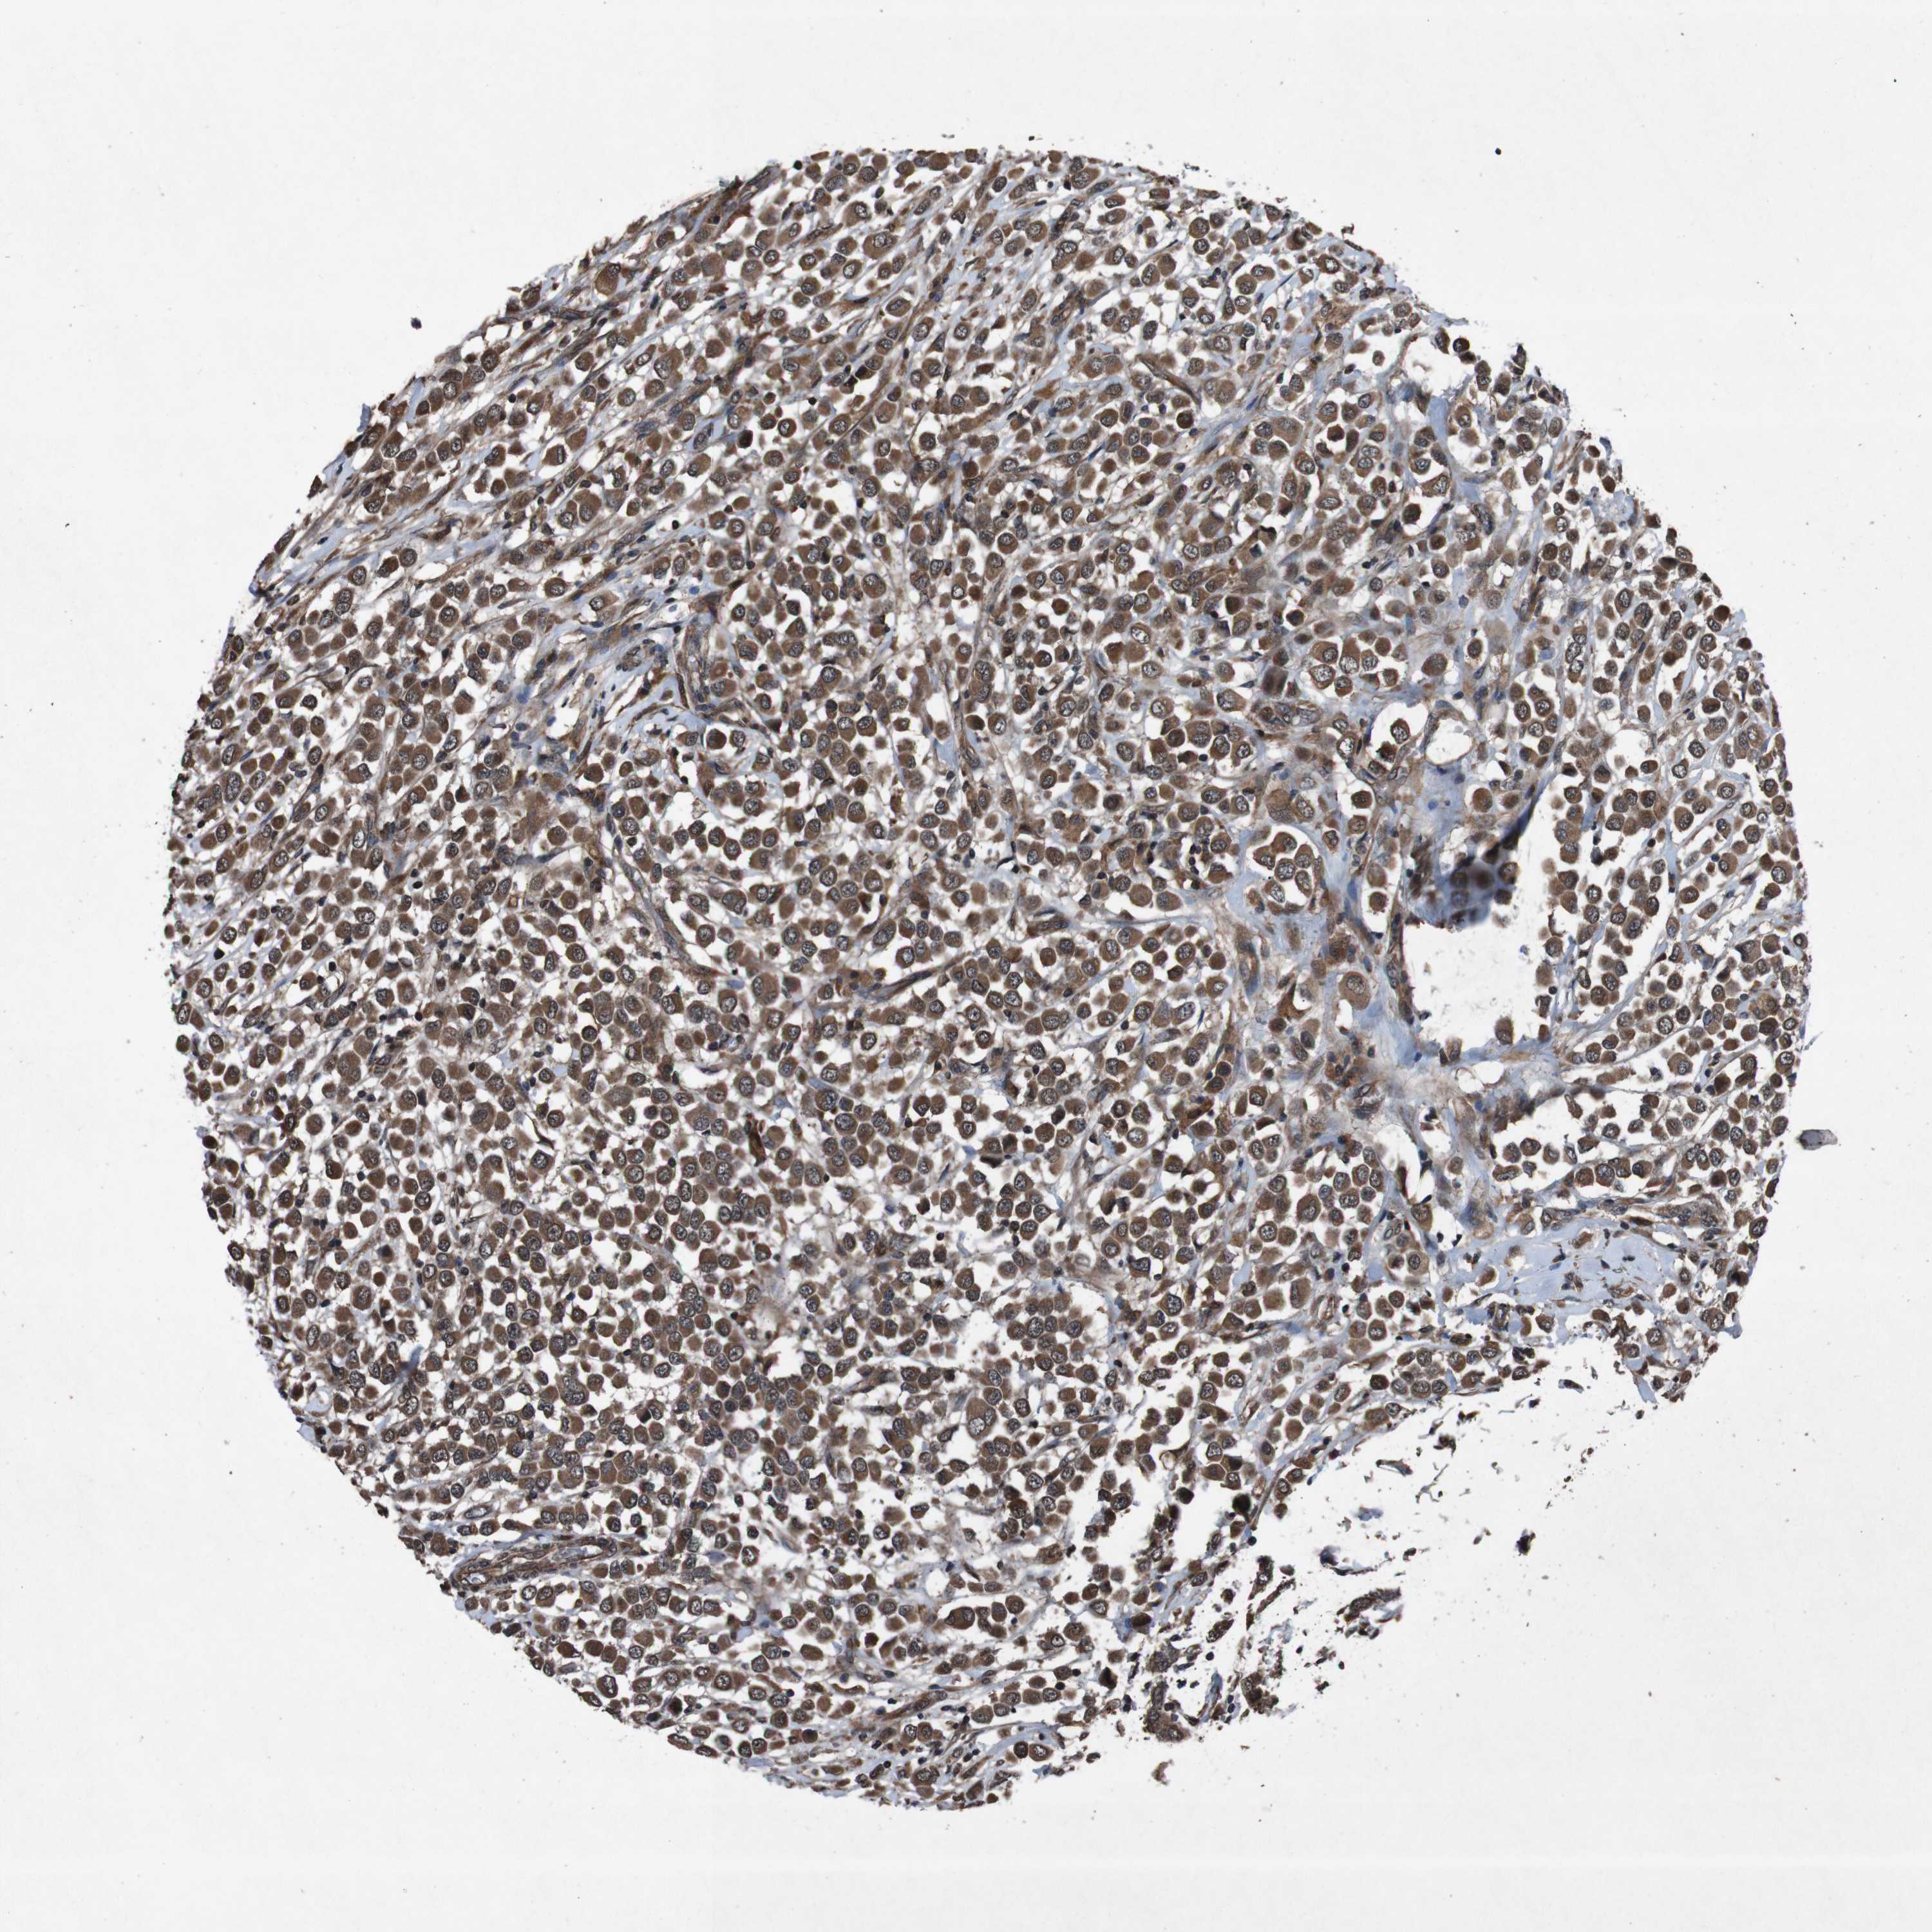

BRCA TCGA BRCA VALIDATION PROTEIN EXPRESSION

ANTIBODIES

AND

VALIDATION